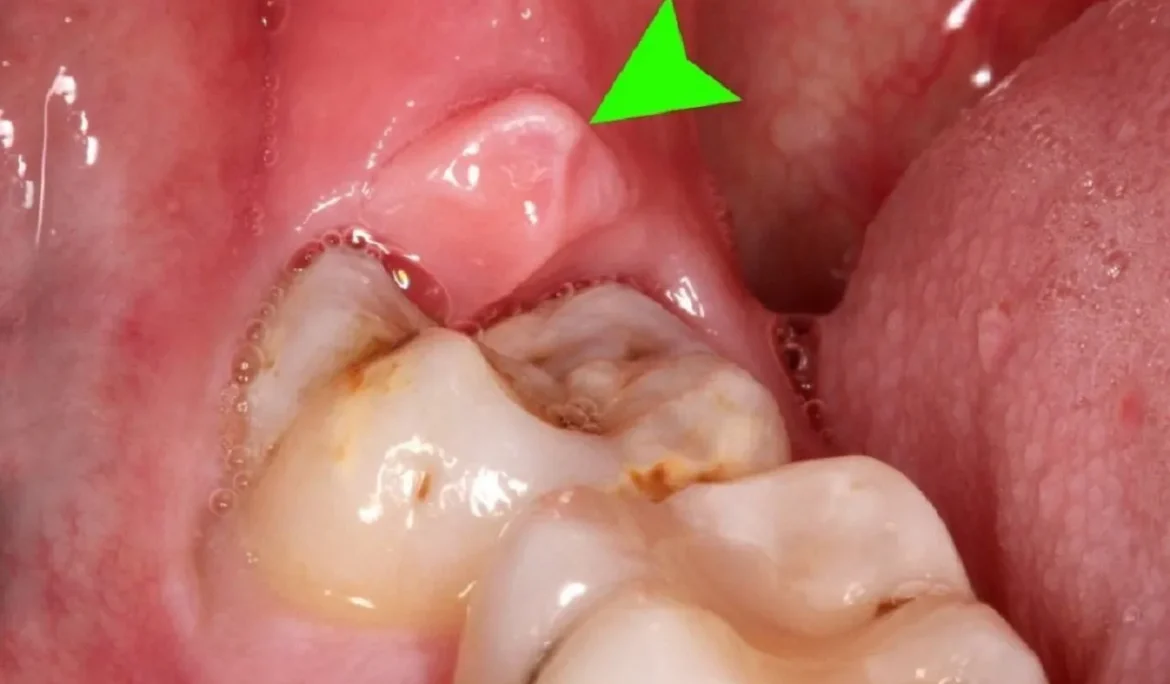

Sưng nướu răng là một trong những tình trạng rất nhiều người mắc phải hiện nay. Trong đó, tới hơn 80% người bị mắc sưng nướu ở

Hiện nay, hiện tượng sưng nướu răng có mủ đang ngày càng phổ biến ở nhiều người. Đây là một bệnh răng miệng nghiêm trọng có thể